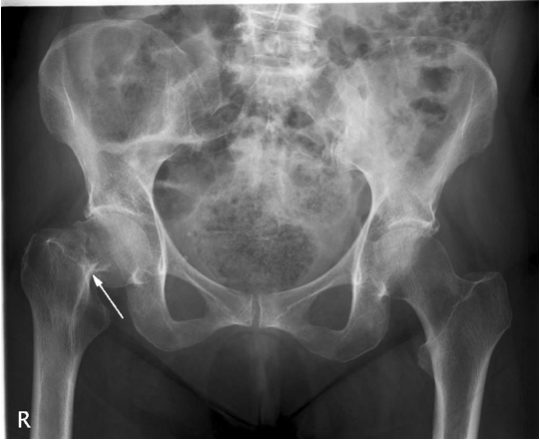

Наиболее частые изменения на рентгенограммах и их описание:

Вывих ТБС. Головка бедренной кости смещена и выходит на пределы вертлужной впадины.

Перелом. Имеет вид линии или щели. Чаще всего располагается в области шейки бедренной кости.

Деформирующий остеоартроз. На ранних стадиях рентгенологические признаки отсутствуют. Позже о патологии говорит сужение суставной щели.